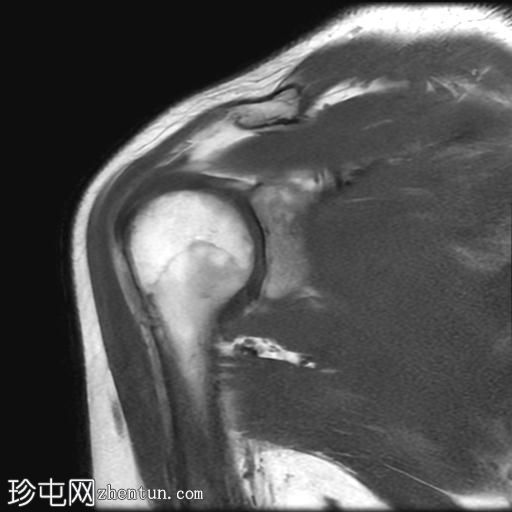

MRI

冠状位

T2加权像

T1加权像

冠状位PD加权像

脂肪抑制像

矢状位

PD加权像

肩袖钙化性肌腱炎:冈下肌腱上部纤维可见约7 x 14 mm的低信号病灶

冈上肌腱滑囊侧纤维可见轻度增高液体信号,提示肌腱病

肩峰II型

肩峰下滑囊可见轻度液体信号